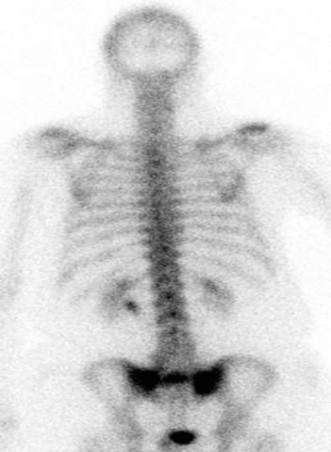

A 73-year-old man with a history of hypertension and hyperlipidemia presents to your office with right hip pa…